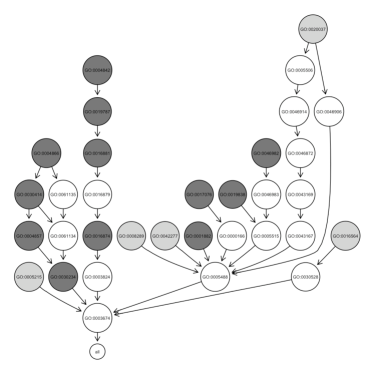

The pathways specific to early PD show a great involvement of the immune system, which is greatly stimulated by inflammation especially located in particular brain regions (mainly substantia nigra). Indeed, we identified: GO:0006952 i.e. defense response, GO:0045087 i.e. innate immuno response also visualized in Figure 3, GO:0006955 i.e. immune response and GO:0030097 i.e. hemopoiesis.

|

| (a) early PD patients | (b) controls |

From Figure 3 it is clear that since the early stages of PD the innate immune system is severly compromised: the body is highly subjected to the invasion and proliferation of microbes (like bacteria or viruses), resulting in a debilitated organism, less effective in fighting the consequent inflammation.